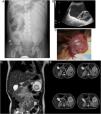

A-C) Hallazgos radiológicos y quirúrgicos del caso A. A) Radiografía de abdomen en decúbito supino mostrando efecto masa en hemiabdomen izquierdo, desplazando las asas intestinales hacia el hemiabdomen derecho. No se observan signos de obstrucción intestinal. B) Ecografía abdominal de alta resolución en escala de grises mostrando gran lesión quística con contenido ecogénico en su interior, septos internos y otra lesión seudosólida en su interior. C) Imagen intraoperatoria donde se evidencia gran masa multiquística rosácea de gran tamaño (15×9×3cm). D y E) Hallazgos radiológicos del caso B. Imágenes de RMN adquiridas de manera multifásica en planos coronal (D) y axial (E) tras administrar gadolinio intravenoso. Se identifica lesión redondeada de aproximadamente 5,3cm en los 3 ejes situada en el hipocondrio izquierdo de contenido probablemente hemorrágico, delimitada por imagen de cápsula-seudocápsula hipointensa. No presenta organodependencia, signos de edema ni infiltración de las estructuras adyacentes.

Caso ANiño de 3 años de edad, sin antecedentes de interés, acude a urgencias por dolor abdominal difuso de 3 días de evolución, con defensa a la palpación en hemiabdomen izquierdo. Había sido valorado una semana antes por episodio clínico similar asociado a fiebre y vómitos, resuelto con tratamiento conservador. Se solicita radiografía de abdomen con efecto masa en hemiabdomen izquierdo y ecografía abdominal en la que se objetiva la existencia de una gran lesión quística intraabdominal (figs. 1A y B). Ante el empeoramiento clínico del paciente se realiza laparotomía exploradora, encontrándose una gran tumoración quística dependiente del omento, con base anclada a la curvatura mayor gástrica de la que se realiza exéresis completa (fig. 1C). El estudio anatomopatológico es informado como linfangioma con contenido hemático.

Niña de 4 años valorada en urgencias por dolor abdominal cólico de 5 días de evolución asociado a vómitos. Había presentado episodios similares con anterioridad, siendo resueltos de manera satisfactoria con la administración de enemas. Se realiza estudio ecográfico donde se objetiva la existencia de una lesión multiquística en hipocondrio izquierdo de gran tamaño. En este caso, la estabilidad clínica de la paciente permite realizar una resonancia magnética nuclear (RMN) para completar el estudio y programar la cirugía. Se observa una lesión quística localizada a nivel de mesenterio y en íntimo contacto con la cola del páncreas (figs. 1D y E). Se realiza un abordaje laparoscópico con exéresis de la lesión y anastomosis intestinal laparoasistida. El informe histopatológico resuelve congruente con lesión quística benigna de inmunofenotipo compatible con una lesión vascular de tipo linfangioma (tabla 1).